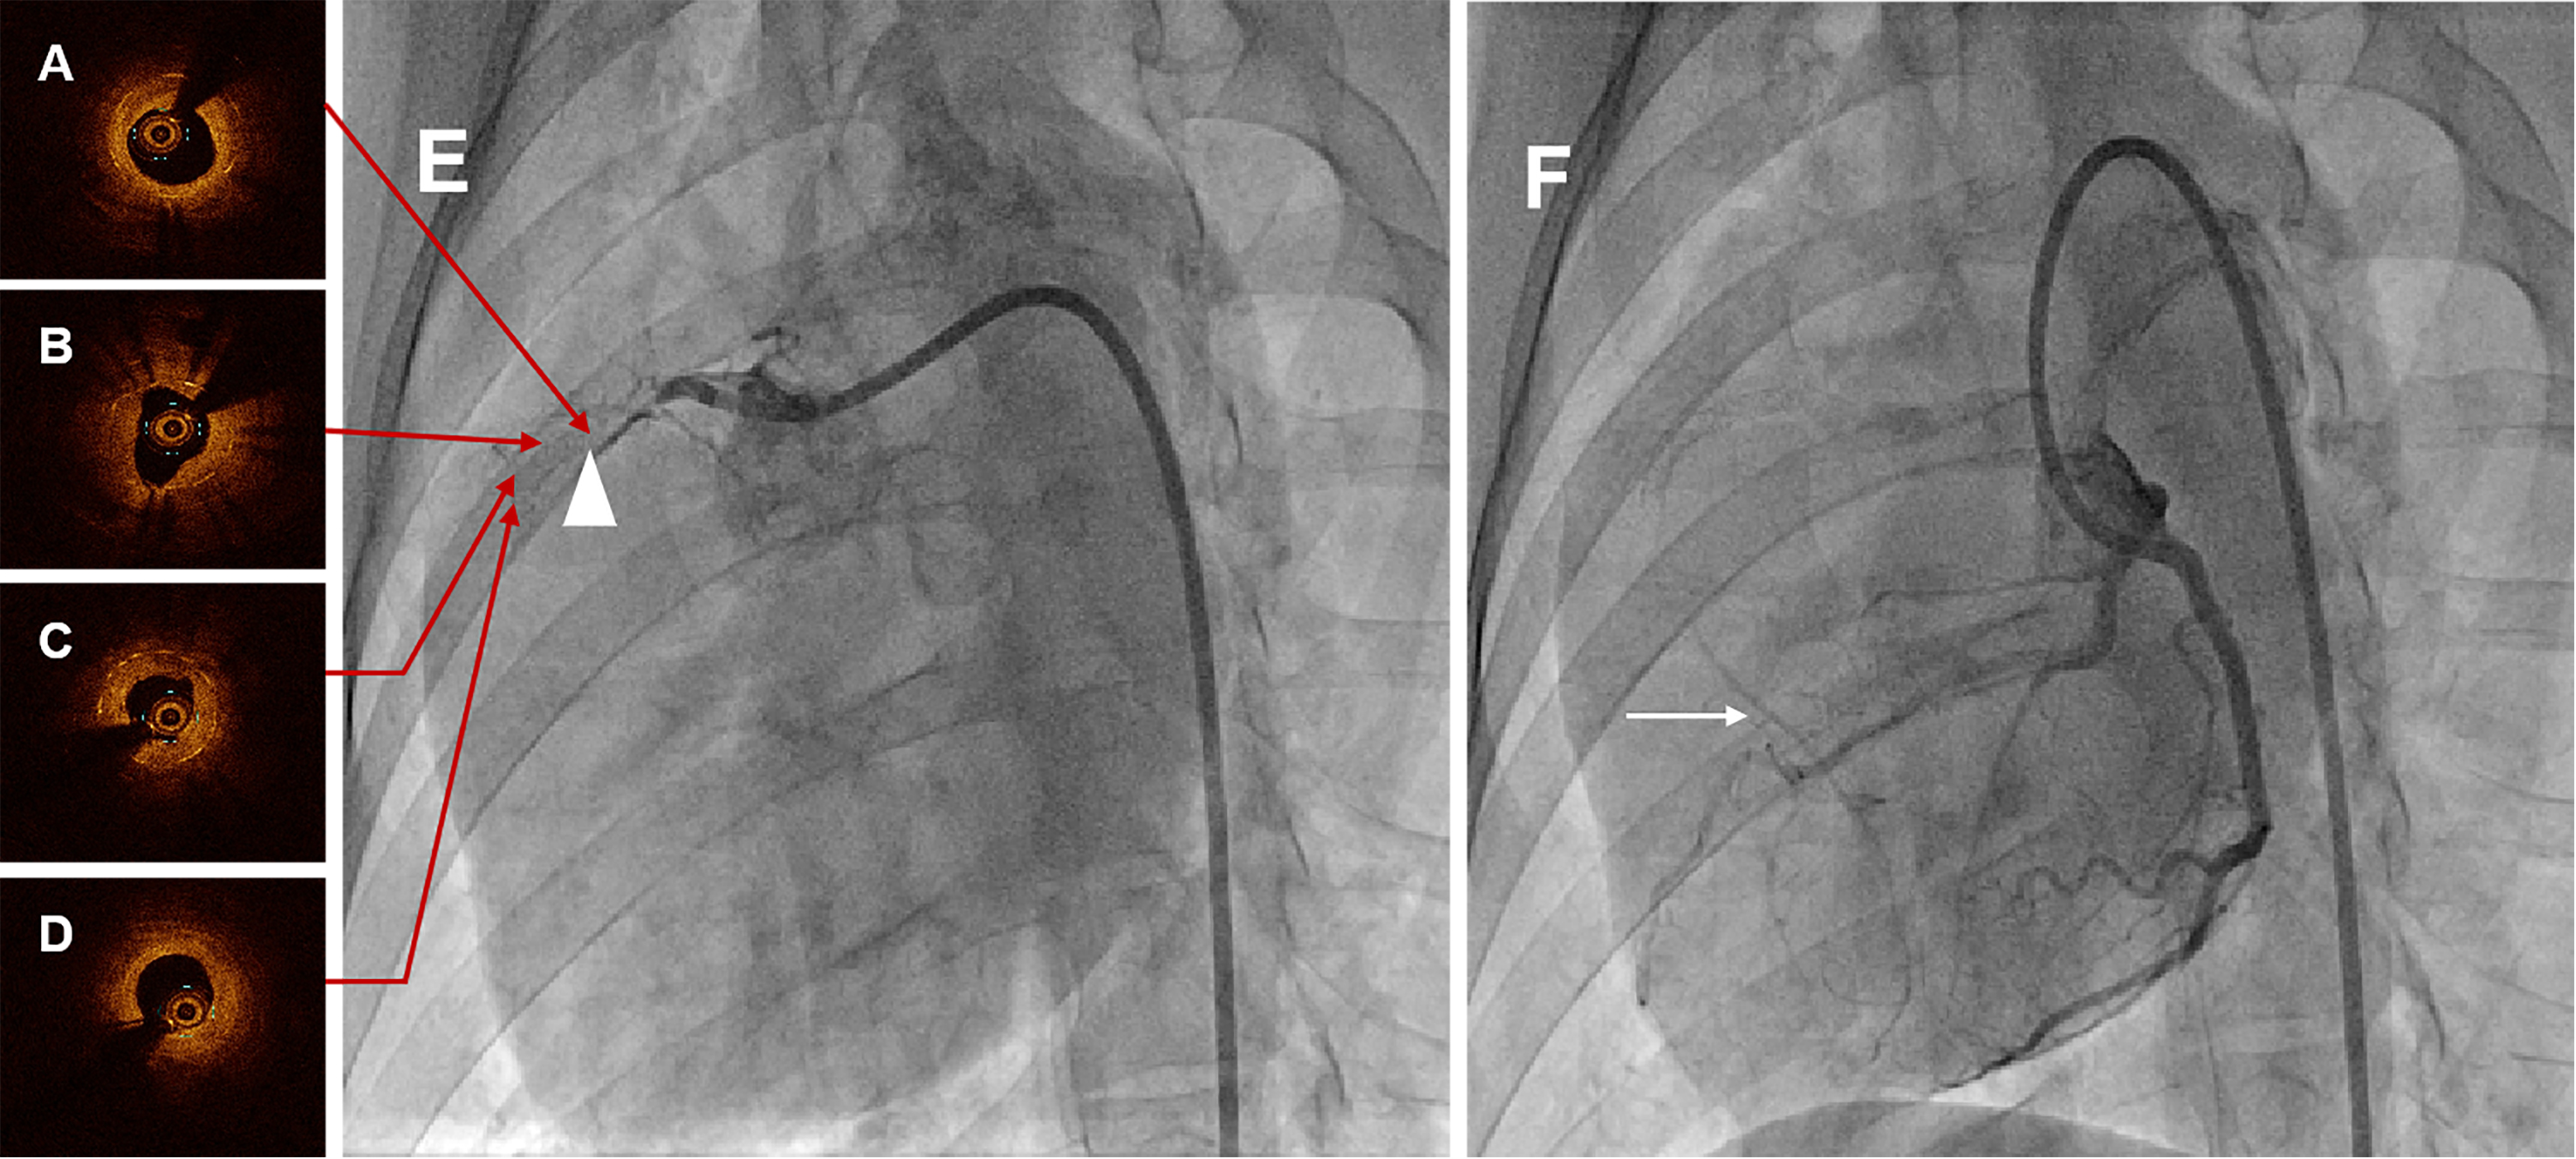

CAG at six months demonstrated total occlusion at the proximal-middle stented RCA segment in all swines, meanwhile with pretty collateral circulation (Rentrop grade 3), shown in Fig. 3E,F and Supplementary Movie 1 and Supplementary Movie 2. Among these animals, two swines were used to constitute occluded stented lesion interventional revascularization and perform the OCT examination. OCT images visualized the diffuse heterogeneous fibrous plaques, as well as organized thrombosis, lipid deposits and several neoatherosclerosis in the occluded segment, shown in Fig. 3A–D and Supplementary Movie 3.

Fig. 3.Representative coronary angiographies and OCT images in swine at six months. (A) Proximal OCT image of the occlusion lesion after interventional recanalization. (B) Proximal-middle OCT image of the occlusion lesion after interventional recanalization. (C) Middle-distal OCT image of the occlusion lesion after interventional recanalization. (D) Distal OCT image of the occlusion lesion after interventional recanalization. Serial OCT images visualized the diffuse heterogeneous fibrous plaques, as well as organized thrombosis, lipid deposits and several neoatherosclerosis in the occluded segment. (E) CAG of RCA in swine at six months, and the white triangle indicated the occluded stented lesion. (F) CAG of LCA in swine at six months, and the white arrow was the collateral circulation. CAG at six months showed total occlusion at the stented segment with pretty collateral circulation. OCT, optical coherence tomography; CAG, coronary angiography; RCA, right coronary artery; LCA, left coronary artery.